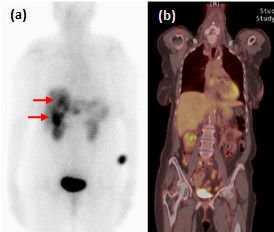

FDG-PET-CT é um exame de baixa sensibilidade na detecção de TNEs bem diferenciados (figura 2), ao passo que a taxa de detecção é alta em pacientes com Ki-67 superior a 15%. Em um estudo prospectivo, a sobrevida mediana de pacientes com FDG-PET-CT negativo e positivo foi de 119,5 meses e 15 meses, respectivamente (P<0,001) (BAHRI, 2014). Um FDG-PET-CT positivo, assim, sugere a necessidade de intervenções terapêuticas mais rigorosas.

Figura 2.

Exames funcionais de tumor neuroendócrino bem diferenciado metastático. Captação em fígado (setas) ao Octreoscan (a), mas não ao FDG-PET-CT (b). Adaptado de Leung et al, 2013.